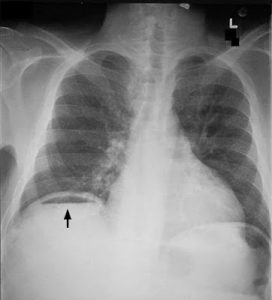

- X-ray abdomen: Erect to look for gas under diaphragm, erect and supine in case of obstruction, renal, ureteric or bladder stones (KUB)